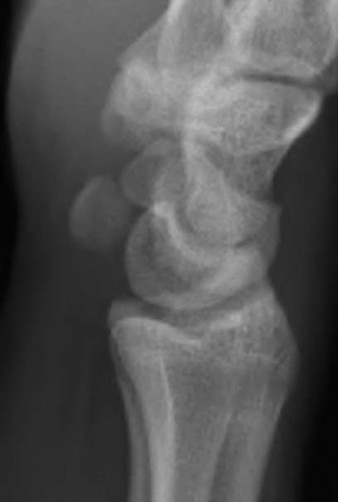

A 35-year-old woman reports wrist pain after a fall onto an outstretched hand. On exam, she has focal tenderness over the wrist snuffbox. A radiograph and CT image are shown in Figures A and B. What is the proper treatment of her injury?